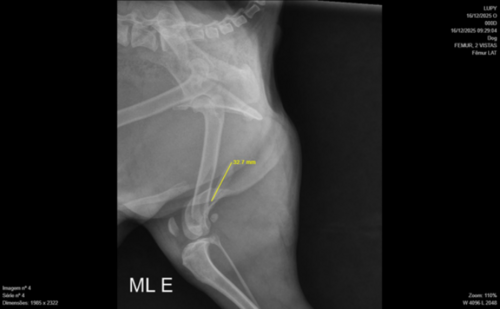

O Lupi é um membro muito querido da nossa família e, infelizmente, ele sofreu um acidente grave e quebrou o fêmur.

Levamos o Lupi a uma clínica especializada em Porto Alegre, e após exames e um Raio-X, o diagnóstico foi confirmado. Ele sente muita dor e o único alívio que tem tido é com doses fortes de Tramadol, um analgésico potente. É doloroso vê-lo dopado e sofrendo, sem a alegria de antes.

A única solução definitiva para que o Lupi pare de sofrer e volte a ter qualidade de vida é uma cirurgia ortopédica de emergência.

Anexamos na página o orçamento completo da clínica e o laudo médico. O custo total do procedimento, incluindo honorários, materiais e internação, é de aproximadamente R$1750,00